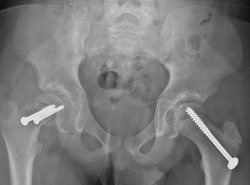

In situ fixation in the opposite hip. Some patients are at higher risk for SCFE occurring on the opposite side. If this is the case with your child, your doctor may recommend inserting a screw into his or her unaffected hip at the same time to reduce the risk of SCFE. Your doctor will talk with you about whether this is appropriate for your child.

In this x-ray, two screws have been inserted in the patient's right hip to stop progression of a slip. A single screw has been inserted in the left hip to prevent SCFE from developing.

Reproduced from Woiczik MR, Pizzutillo PD, Gross RH, Carroll KL: Musculoskeletal effects of Down Syndrome. Orthopaedic Knowledge Online Journal 2012; 10(10). Accessed June 2016.